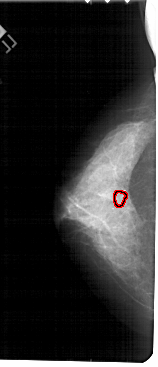

A_1735_1.LEFT_MLO

FILE: A_1735_1.LEFT_MLO.OVERLAY

TOTAL_ABNORMALITIES 1

ABNORMALITY 1

LESION_TYPE CALCIFICATION TYPE PLEOMORPHIC DISTRIBUTION CLUSTERED

ASSESSMENT 4

SUBTLETY 3

PATHOLOGY BENIGN

TOTAL_OUTLINES 1

BOUNDARY